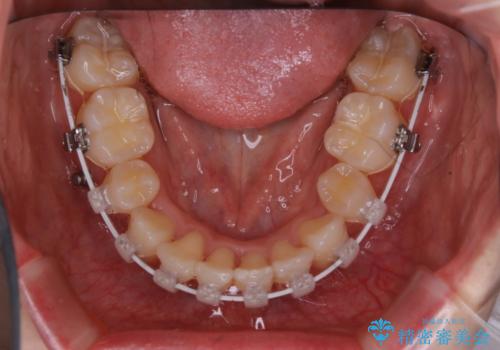

- 矯正装置

- ワイヤー矯正 審美装置

ワイヤー治療の利点について

今回のように不確定要素がある治療の場合、ワイヤー治療なら臨機応変に対応することが可能となります。